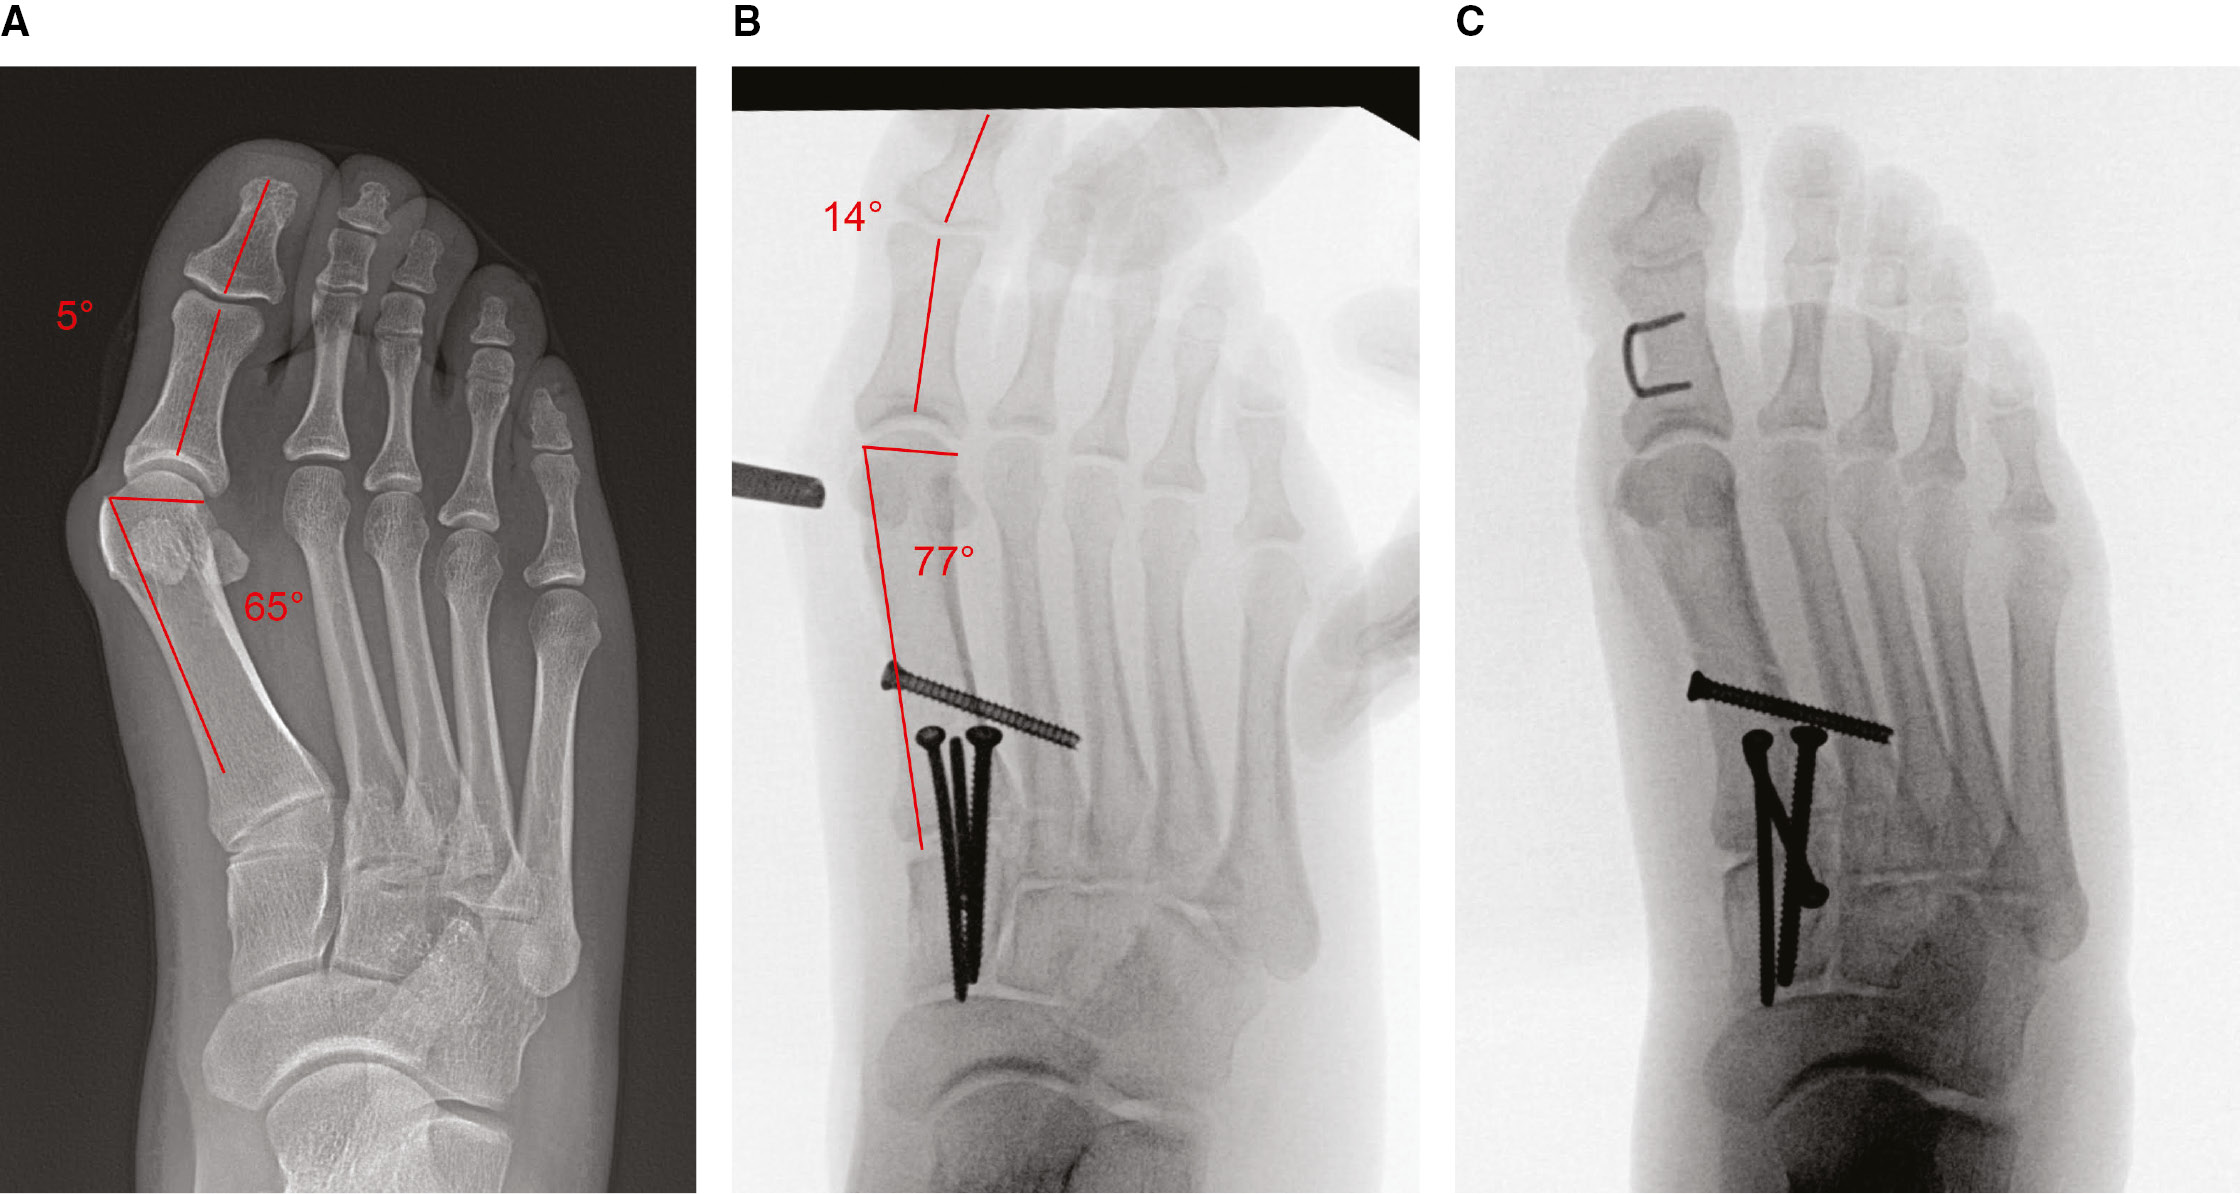

Standing radiographs of the foot are obtained. On the anteroposterior (AP) radiograph, the 1st/2nd intermetatarsal angle (IMA), the hallux valgus angle (HVA), the distal metatarsal articular angle (DMAA), and the angle between the proximal and distal phalanx are measured (Figure 1). No specific degree of interphalangeous deformity delineates the need for treatment, and it is difficult to predict those that will require treatment based on preoperative radiographs secondary to the pronation. Furthermore, the authors do not advocate for a specific DMAA cutoff in decision-making, as the preoperative DMAA measurement may be unreliable given the rotation of the metatarsal. Further guidance on the management of these scenarios is detailed in the Operative Technique.

Figure 1. Preoperative radiographic assessment of a 15-year-old female with recurrent adolescent hallux valgus after proximal 1st MT opening wedge osteotomy and distal soft tissue realignment. (A) Intermetatarsal angle (IMA). (B) Hallux valgus angle (HVA). (C) Angle between the proximal and distal phalanges. (D) Distal metatarsal articular angle (DMAA).

A screw can also be placed transfixing the proximal shafts of the first and second metatarsal, thus holding the correction of the IMA and pronation. In cases where joint congruency is a concern, which is common in juvenile hallux valgus, the IMA and rotation are corrected first with the Lapidus procedure. An intraoperative assessment is then made on the DMAA. If the joint is still in valgus, a distal osteotomy is used to correct the deformity. The authors most commonly utilize a medial closing wedge osteotomy, but a biplanar chevron can also achieve correction (Figure 7).

Figure 7. (A) Preoperative standing AP radiograph of 18-year-old male with symptomatic hallux valgus. The DMAA is 25 degrees and interphalangeal angle between the proximal and distal phalanx is 5 degrees. (B) Intra-operative evaluation of the DMAA and interphalangeal angle after correction and fixation with a Lapidus procedure. Note that the DMAA is now 13 degrees, so the decision was made to perform a distal soft tissue realignment rather than a distal osteotomy. However, the interphalangeal angle now measures 14 degrees. (C) Intra-operative radiograph after performance of a proximal phalanx medial closing wedge osteotomy.